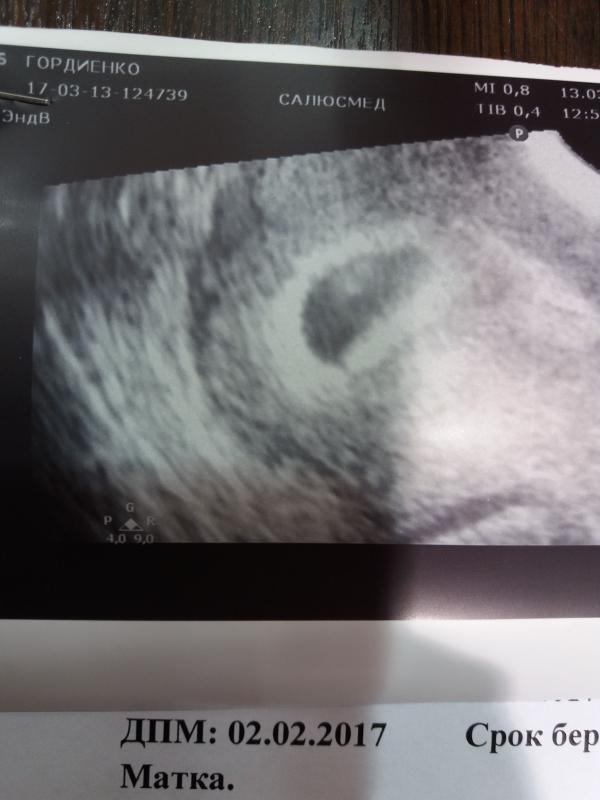

😍😍😍Моя фасолинка😍😍😍

@e.afanaseva да, кстати, на экране больше на креветку похоже было😂😂😂, но муж этого не видел. Кума снимок посмотрела - воообще выдала: опять пацан, глянь писюн торчит.😲😲😲говорю: где??? Ему 5 недель!!!!

@mama1984mariya Поздравляю Вас 😊Прочитала у вас узи подписано :моя фасолинка 😊😊😊😊Мы так же сказали с мужем когда увидели первый раз на Узи нашу малышку 😊Легкой беременности Вам 🌺